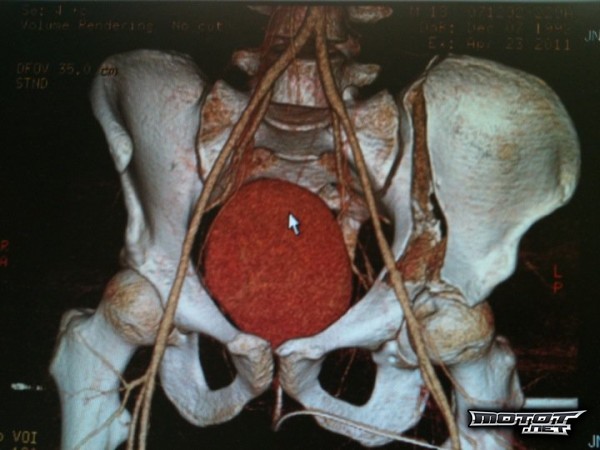

- Lantio.jpg

- Auts, mitä täs on käyny? :o20.3.2012 15:10